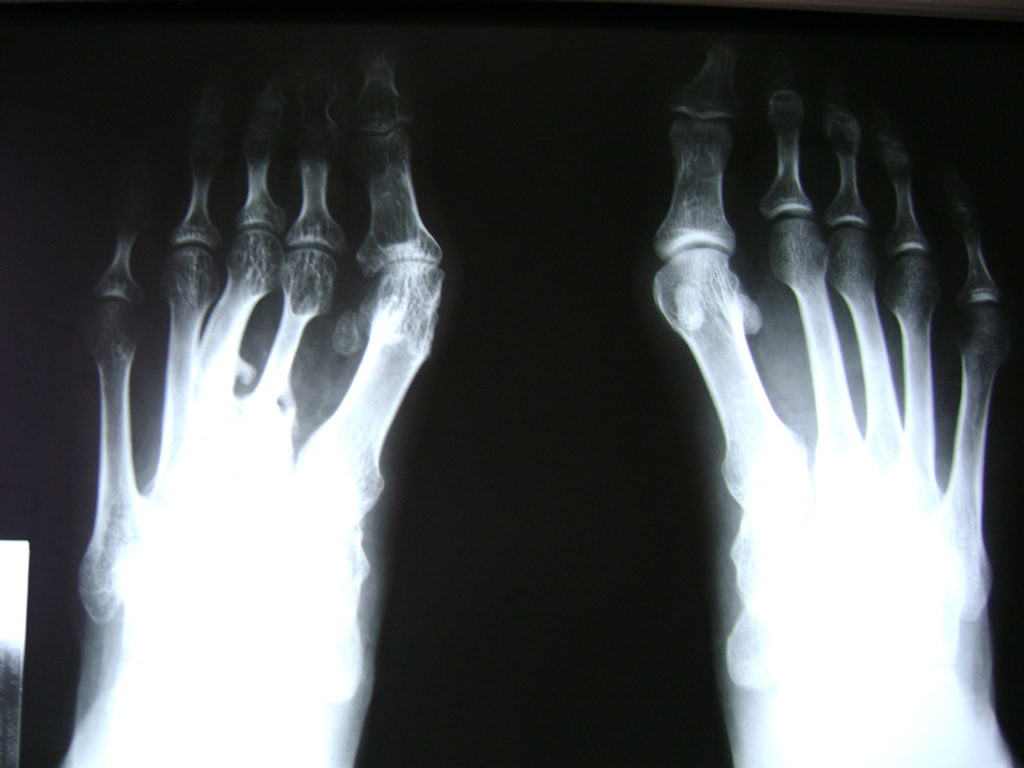

Cirugías de Pies

Las deformidades de los pies heredadas o adquiridas son el objeto principal de la cirugía reconstructiva del pie; sobretodo cuando producen dolor con el apoyo debido a una sobrecarga localizada o bien al no ser capaces de adaptarse a un calzado apropiado.

El pie consta de numerosas articulaciones con un mínimo movimiento cuya finalidad es adaptarse al terreno en cualquier situación. Cuando estas articulaciones que soportan grandes cargas y realizan movimientos sutiles se deterioran o funcionan de manera inapropiada, se suelen fusionar con el fin de evitar el dolor o bien restablecer la forma natural del pie y del apoyo.